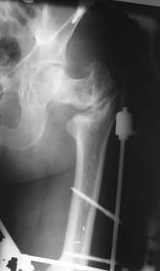

Возможно, пример (в приложении) поможет Вам определиться с выбором тактики лечения (у нашего пациента, кроме тугого ложного сустава вертельной области, сложная деформация н/3 бедренной кости; т.к. это не имеет значения к обсуждаемой теме - оставил "за кадром"). Как Вы видите, мы в данном случае не вводили чрескостные элементы в зону установки имплантата. При отказе от наложения опоры на таз (кстати, она не обязательно может быть громоздкая спицевая; арки со стержнями-шурупами, введенными в крыло подвздошной вполне достаточно) "не удивляйтесь", если опора со стержнями-шурупами, введенными в вертельной области в скором времени дестабилизируется, возникнет воспаление мягких тканей у чрескостных элементов. Такая опора "имеет на это право": нагрузка конечности от вершины дистального фрагмента до кончиков пальцев ляжет на нее. А двух-трех введенных рядом стержней-шурупов, как их не разноси от фронтальной плоскости, в данном

случае явно недостаточно для адекватной фиксации. + для того, чтобы выбрать оптимальные чрескостные элементы для промежуточной и дистальной опор, можете воспользоваться атласом